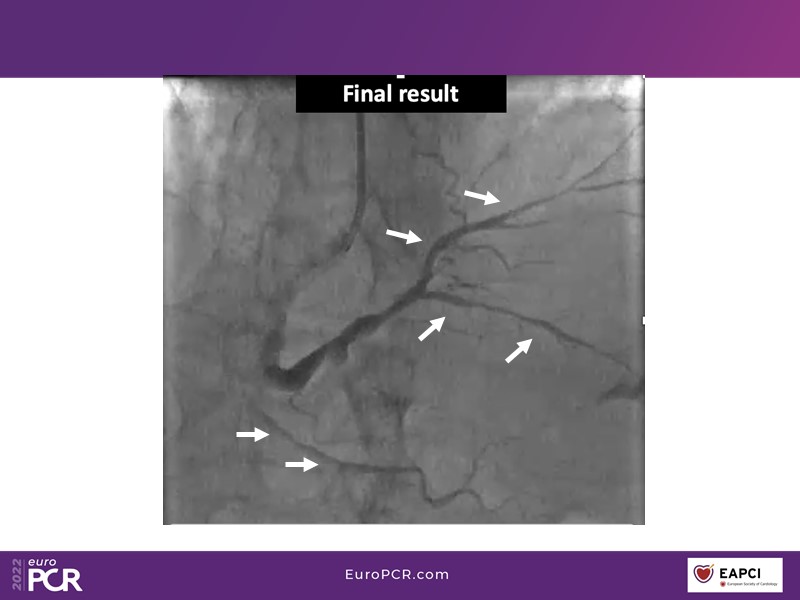

- To find out more about the application and mechanism of a sirolimus coated balloon for coronary artery disease treatment with case presentations in complex settings

- To understand how useful is a DES and DCB stent platform in complex coronary artery disease settings with case demonstrations and follow-up in diabetes mellitus